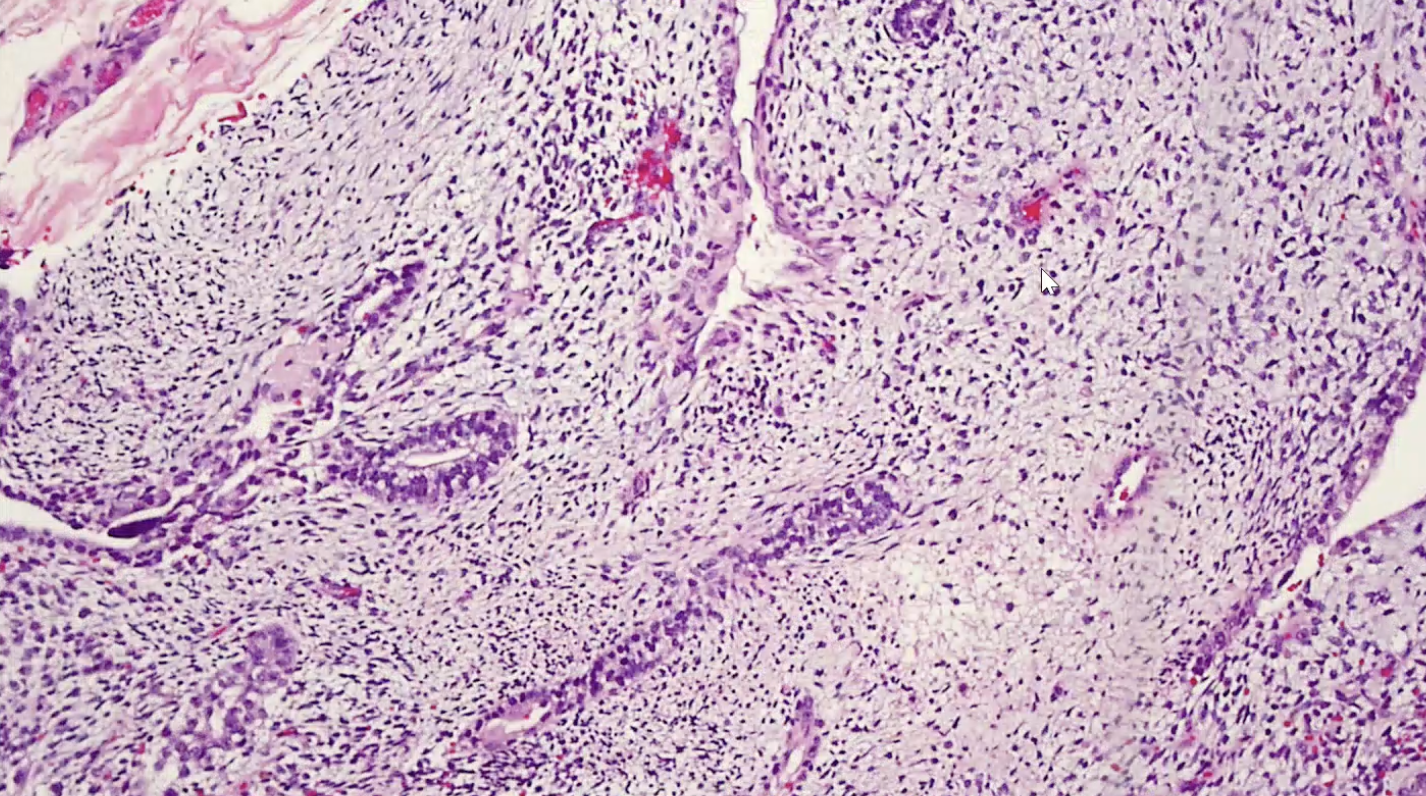

Granulomatous Orchitis